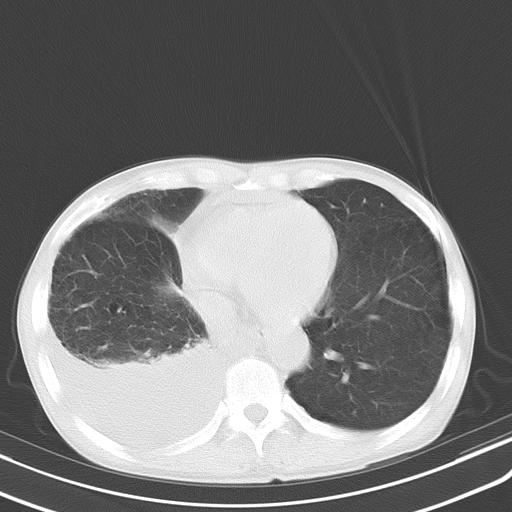

男性 75  咳嗽 一周前发热最高达39

右肺继发型tb并右侧tb性胸腔炎,右侧胸腔大量积液并右下肺膨胀不全,慢支肺气肿、多发肺大泡。建议抽胸水实验室检查并复查排除恶性在占位。

右上肺继发型肺结核,右胸腔中等量积液。

左上肺大泡。

结核的基础上有纵隔淋巴结肿大,右侧有胸水,但右侧纵隔反而窄,说明有肺有不张。

再就是右下肺有块影,和不张混合,还是不能除外肺癌。

1)右肺继发型肺结核。2)左肺胸膜下多发性肺大泡。3)右侧胸腔积液。